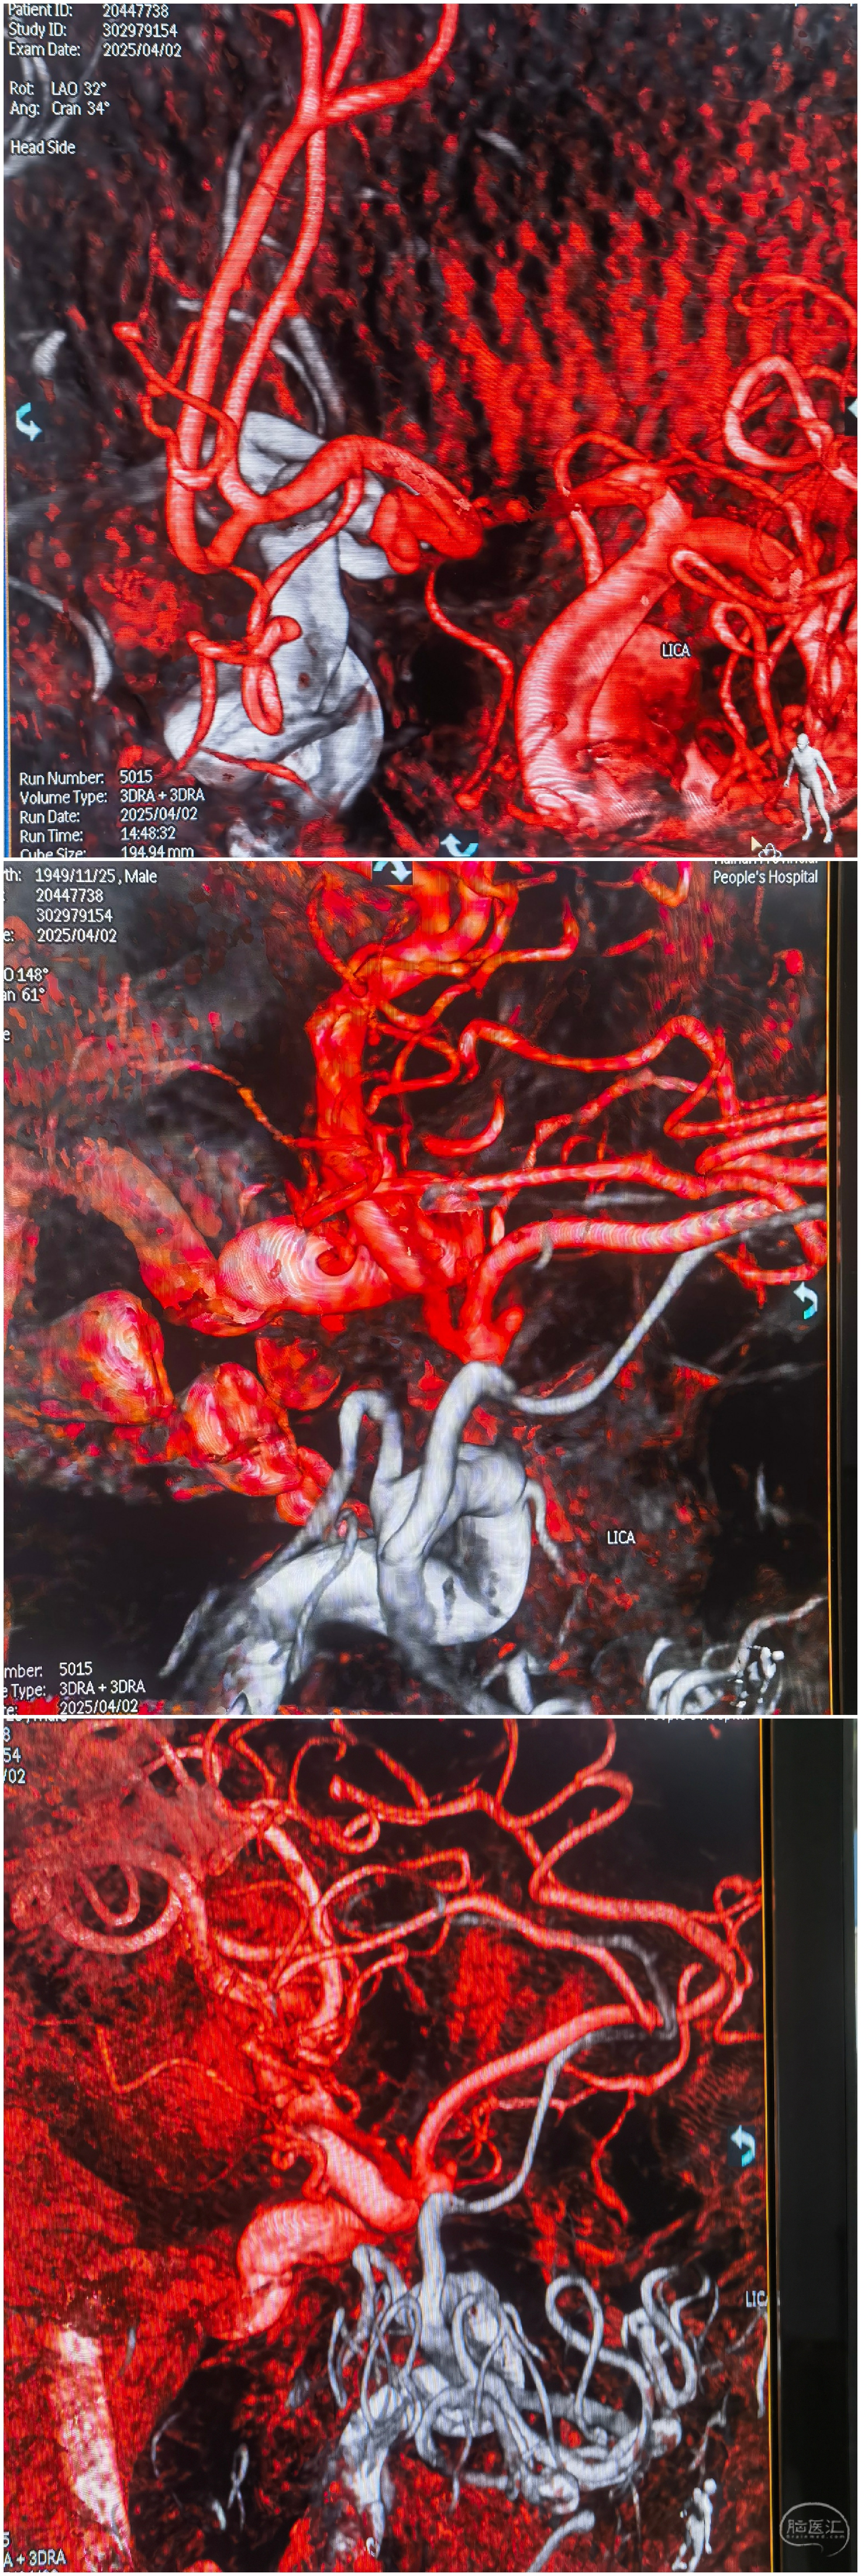

3D重建

双侧颈内3D融合